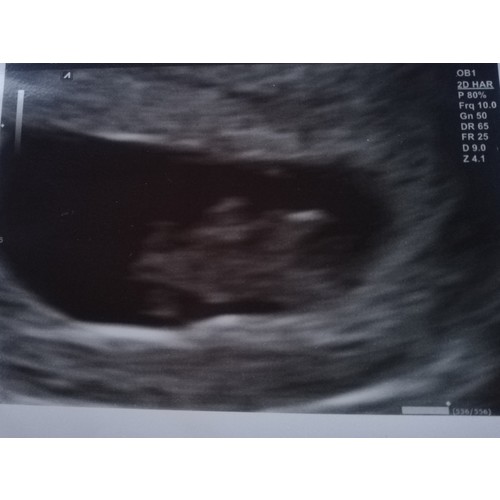

Dit was de mijne met 8+5 😍